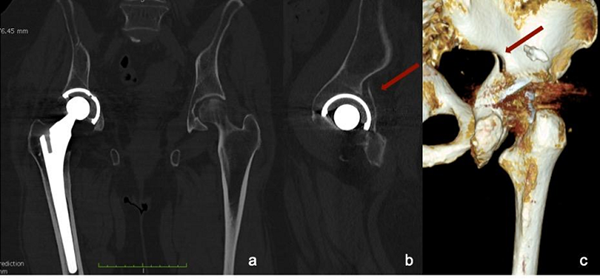

2:骨盆的CT掃描。 (a)冠狀視圖顯示髖臼杯略向內(nèi)側(cè)突出;

(b)髖關(guān)節(jié)矢狀面顯示髖臼后壁骨折。骨折的三維重建是可見的(c),但是其擴(kuò)展被圖像偽影隱藏了。

他們以一名75歲的女性為例,該女性在家庭創(chuàng)傷事件發(fā)生后進(jìn)入急診室。該患者有右髖嚴(yán)重髖關(guān)節(jié)病的病史,在使用非骨水泥THA治療前已有十年治療。醫(yī)生對她的骨盆進(jìn)行了AP射線照相,對她的臀部進(jìn)行了盤腿掃描,沒有發(fā)現(xiàn)髖臼或莖周圍骨折或松弛的跡象。但是,“通過MAR協(xié)議對骨盆進(jìn)行CT掃描”顯示,盡管髖臼杯未移位,但髖臼后壁確實有骨折。